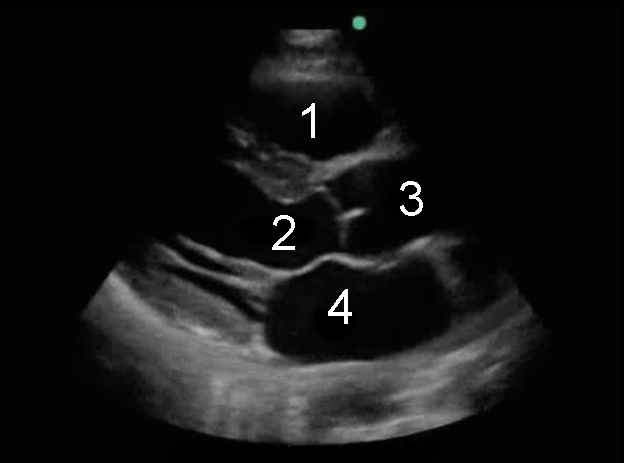

Parasternal Long Axis (PLAX) in Diastolic

1. Right Ventricle (RV)

2. Left Ventricular Outflow Tract (LVOT)

3. Aorta

4. Left Atrium (LA)